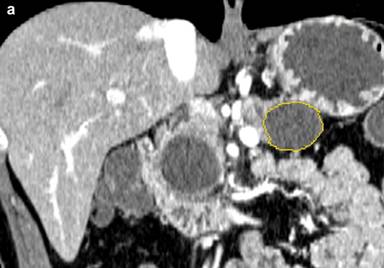

For measurement of the cyst diameter and volume, commercially available software (CT Oncology; Siemens Medical Solutions) was used on an image-processing workstation (Leonardo Workstation, syngo® 2008A MultiModality Workplace (VE26A) platform; Siemens Healthcare, Erlangen, Germany). Two independent investigators (H.C. and P.R.) with one and two years of experience using the software, respectively, performed the measurement on pancreatic parenchymal phase images. Pancreatic parenchymal phase was selected due to the superior conspicuity of the lesions in this phase. The application of this software in the volumetric measurement of abdominal masses has been described previously [13, 18]. The graphic user interface is divided into 4 screens: axial, coronal, sagittal and 3D views. Once the investigator identifies the pancreatic mass by drawing an approximate line across it, the software selects the entire lesion. This is achieved by three-dimensional reasoning by the software to remove neighboring normal pancreatic tissue, hence, generating a volume of interest around the drawn line and extends the segmentation on the basis of histogram analysis within the generated volume on interest (Figure 2). The selections can be edited by the investigator in x, y, and z planes, if necessary.

Figure 2. Coronal (a.), axial (b.), sagittal (c.) and three dimensional (d.) CT images of a histopathologically proven pancreatic tail mucinous cystic neoplasm in a 39-year-old man. Despite a dilated pancreatic duct no connection was visualized on endoscopic ultrasound with the cyst. Borders of cyst are marked with yellow line by the software. CT volumetry (22.3 mL) and an elongation value (0.67) for the cyst were automatically generated by the software once the measurement was finalized by the observer. Pancreatic head cyst was not segmented because of apparent connection with the pancreatic duct that was dilated. Also, note that the patient was a male with mucinous cystic neoplasm, an extremely rare occurrence. |